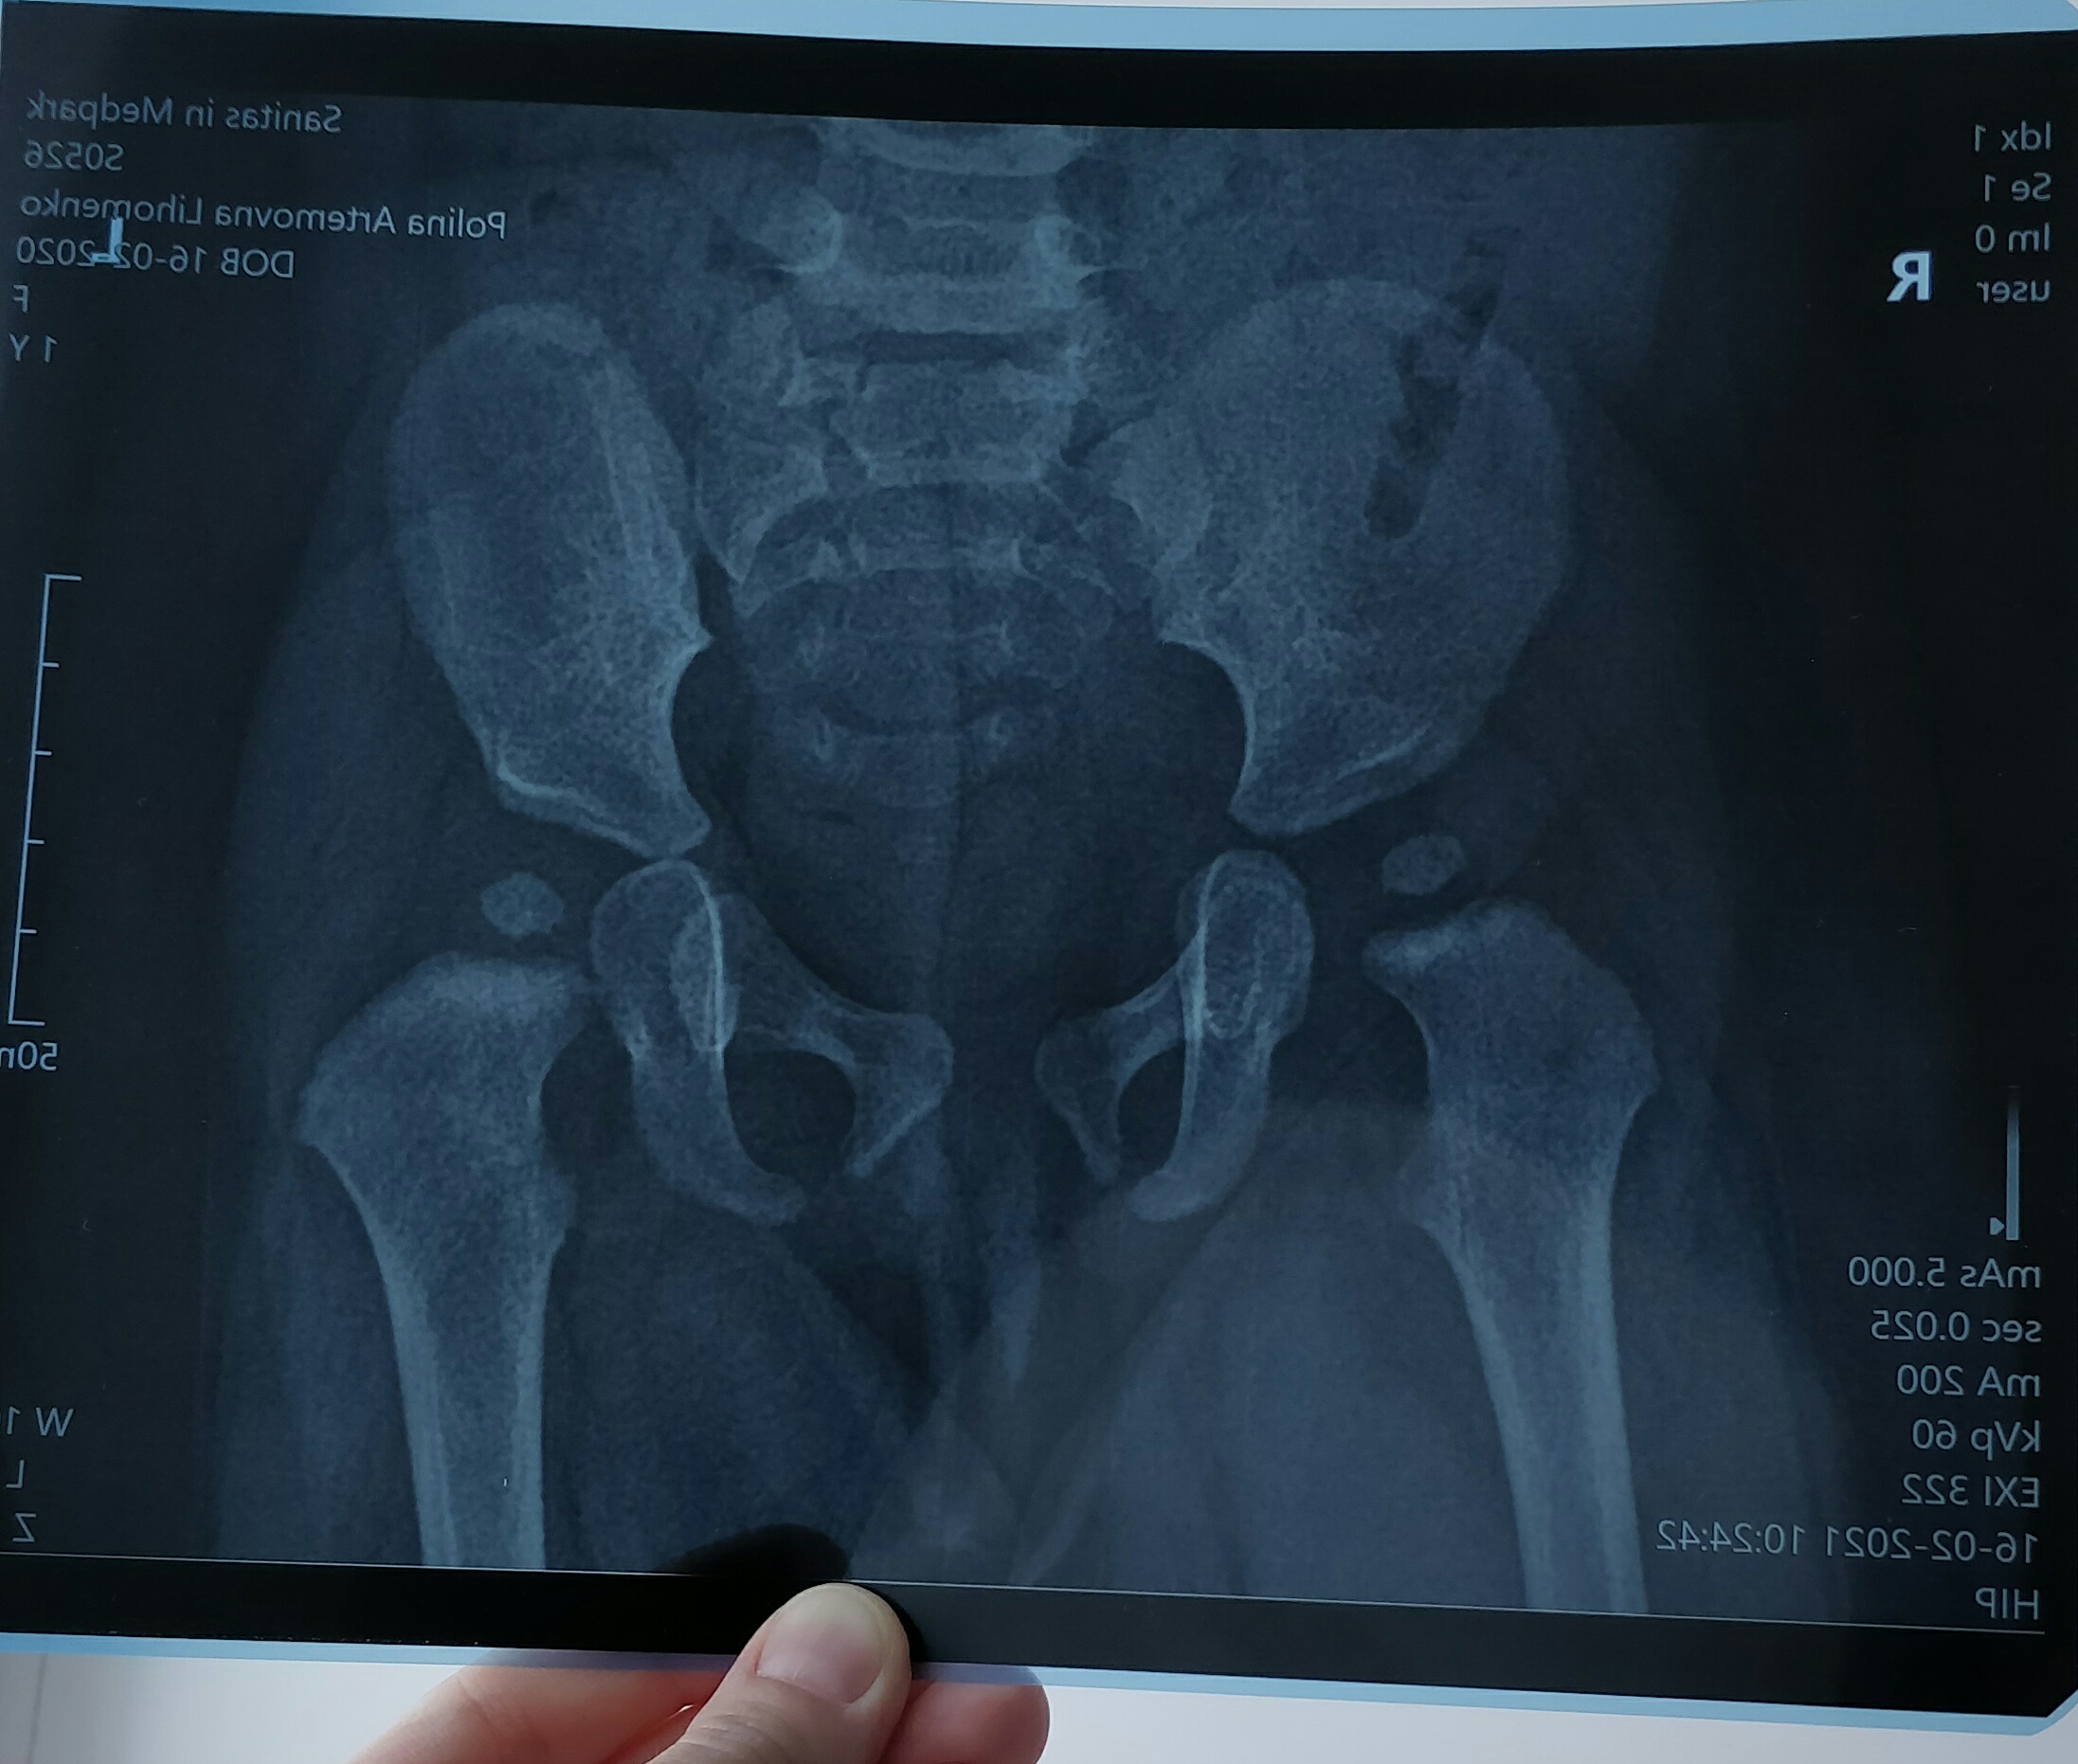

Рентген ТБС: Нормальные показатели